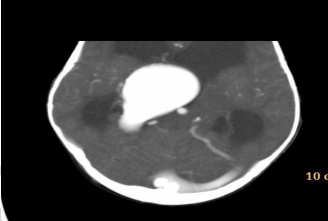

Um lactente de 3 meses de vida é encaminhado para atendimento em razão de aumento do perímetro cefálico (PC). A mãe não havia realizado pré-natal, mas nega uso de substâncias ou processos infecciosos durante a gestação. A criança foi encaminhada para avaliação cardiológica em razão de sopro cardíaco. Ao exame, percebe-se taquipneia leve, PC superior a 2 desvios-padrão, ausência de dismorfismos faciais e fontanela anterior aberta e abaulada. Tônus e trofismo estão preservados, e o paciente eleva os quatro membros contra a gravidade e tem reflexos normoativos. A tomografia de crânio é apresentada na figura. A respeito das informações apresentadas, qual é o diagnóstico para esse paciente?Provas